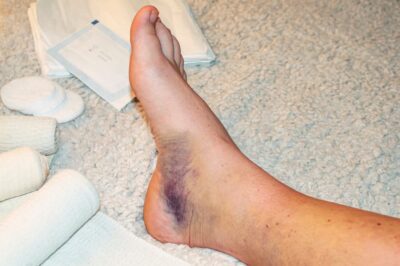

Sưng đau, bầm tím và khó đứng hoặc đi lại

Khi cổ chân bị tổn thương, phản ứng ban đầu thường là sưng tấy do các mô mềm bị viêm, phù nề hoặc tích tụ máu sau va chạm. Cảm giác đau kéo dài hoặc tăng lên khi vận động sẽ gây cảm giác khó chịu rõ rệt, thậm chí mất khả năng đứng vững hoặc đi lại bình thường.

Bên cạnh sưng, nhiều trường hợp còn xuất hiện màu sắc bầm tím quanh vùng cổ chân do các mao mạch bị vỡ. Hiện tượng này thể hiện rõ mức độ tổn thương mô mềm, phản ánh rằng tổn thương đã ảnh hưởng sâu vào các cấu trúc bên trong. Người bị chấn thương thường cảm thấy vùng bị đau nhức dữ dội hoặc âm ỉ, và có thể đi kèm cảm giác tê liệt hoặc nóng rát, ảnh hưởng lớn tới khả năng vận động bình thường hàng ngày.

Trong nhiều tình huống, người bệnh sẽ gặp khó khăn khi cố gắng đứng hoặc đi lại do đau hoặc sưng tấy quá mức, thậm chí có cảm giác vùng cổ chân như bị “kẹp” hoặc “nén chặt”. Các triệu chứng này cần được chăm sóc và xử lý sớm để tránh làm trầm trọng hơn tổn thương cũng như thúc đẩy quá trình lành vết thương diễn ra nhanh hơn.